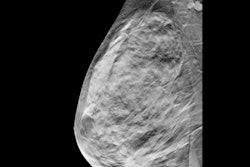

Digital mammography and later digital breast tomosynthesis (DBT) have been replacing film-screen mammography over the last several decades. However, it has not been established if these technological advances have significantly improved diagnostic performance.

"Digital breast tomosynthesis (DBT) is a technological advance that is still based in digital mammography. Improvements in cancer detection are likely related to being able to focus on a plane of tissue in a breast; removing tissue above and below that might obscure a cancer," Lee wrote. "DBT can also reduce 'false-alarms' from overlapping tissue that mimics a breast cancer. However, some limitations of digital mammography may still persist with DBT technology."